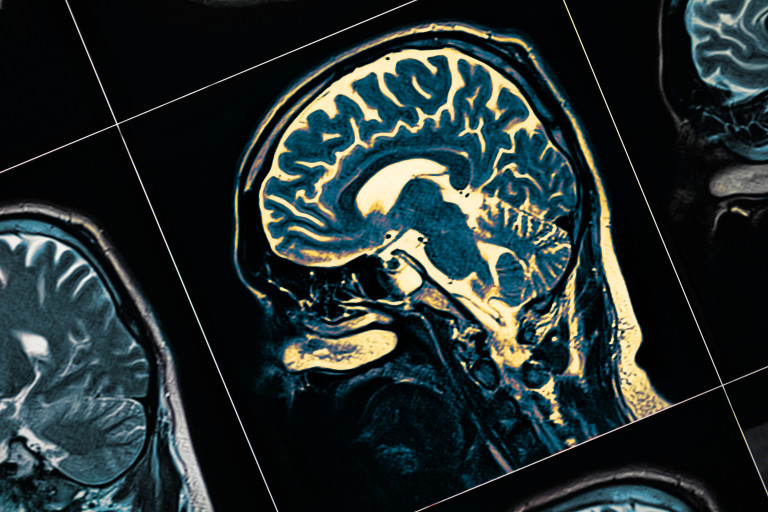

Според неврологията, мозъчната вълна е равномерен модел на електрическа интензивност, който се създава от група неврони, работещи дружно на една периодичност. Честотата на мозъчната вълна е обвързвана с разнообразни неврологични функционалности, сходно на радио- и телевизионните станции, които също излъчват на разнообразни честоти.

Когато сме съсредоточени, когато сътворяваме или връщаме мемоари в съзнанието си, в мозъка ни се следят така наречен гама талази, които са с периодичност от 30 до 100 Hz . Според проучвания от преди две десетилетия, пациентите с болест на Алцхаймер имат доста по-слаби гама талази. Затова и се допуска, че това е един от резултатите на болестта.